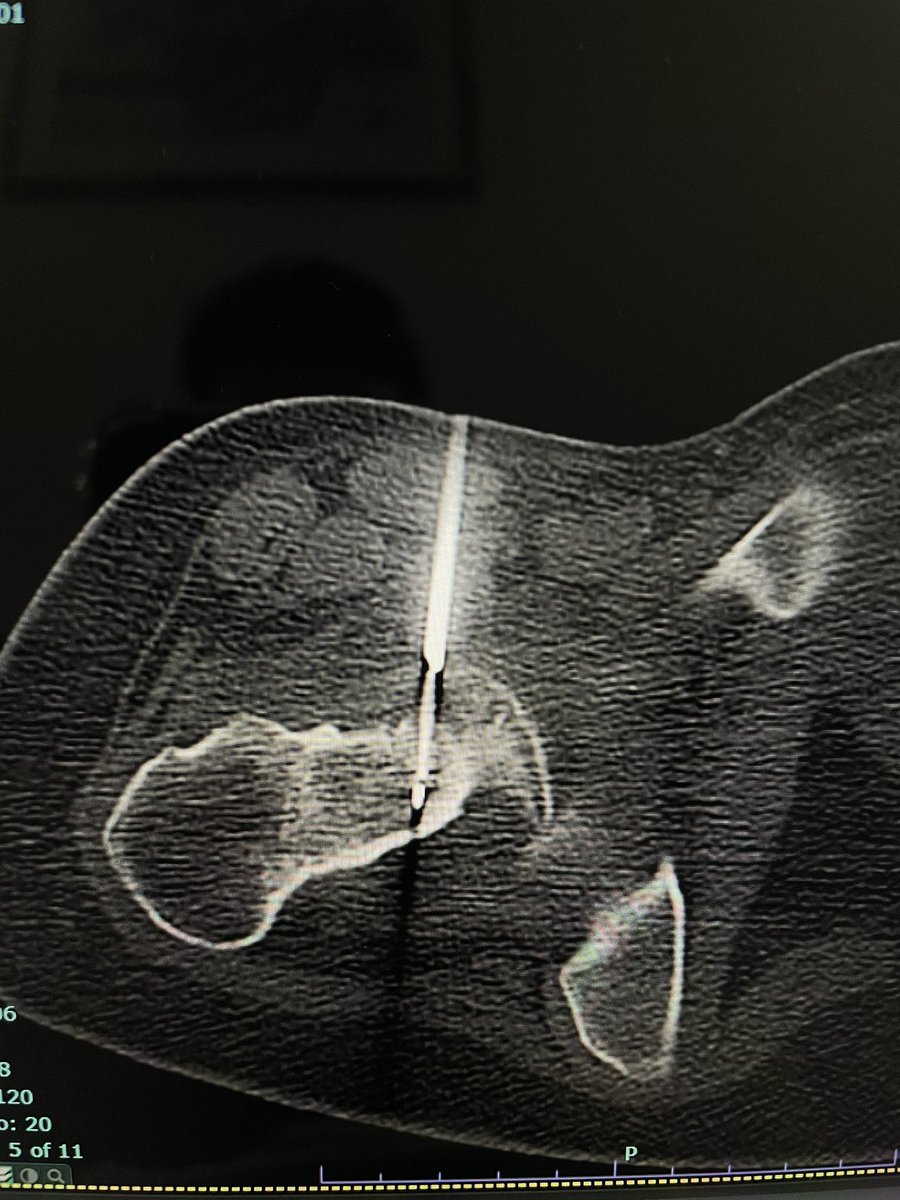

I had an opportunity to perform Intraarticular Osteoid osteoma RFA under GA

@alokmittaldr

CT confirmed it.

19 yr girl with chronic rt hip pain. One of my colleague @samrad77 diagnosed it intraarticular osteoid osteoma- rt femoral neck. I wasn’t sure.